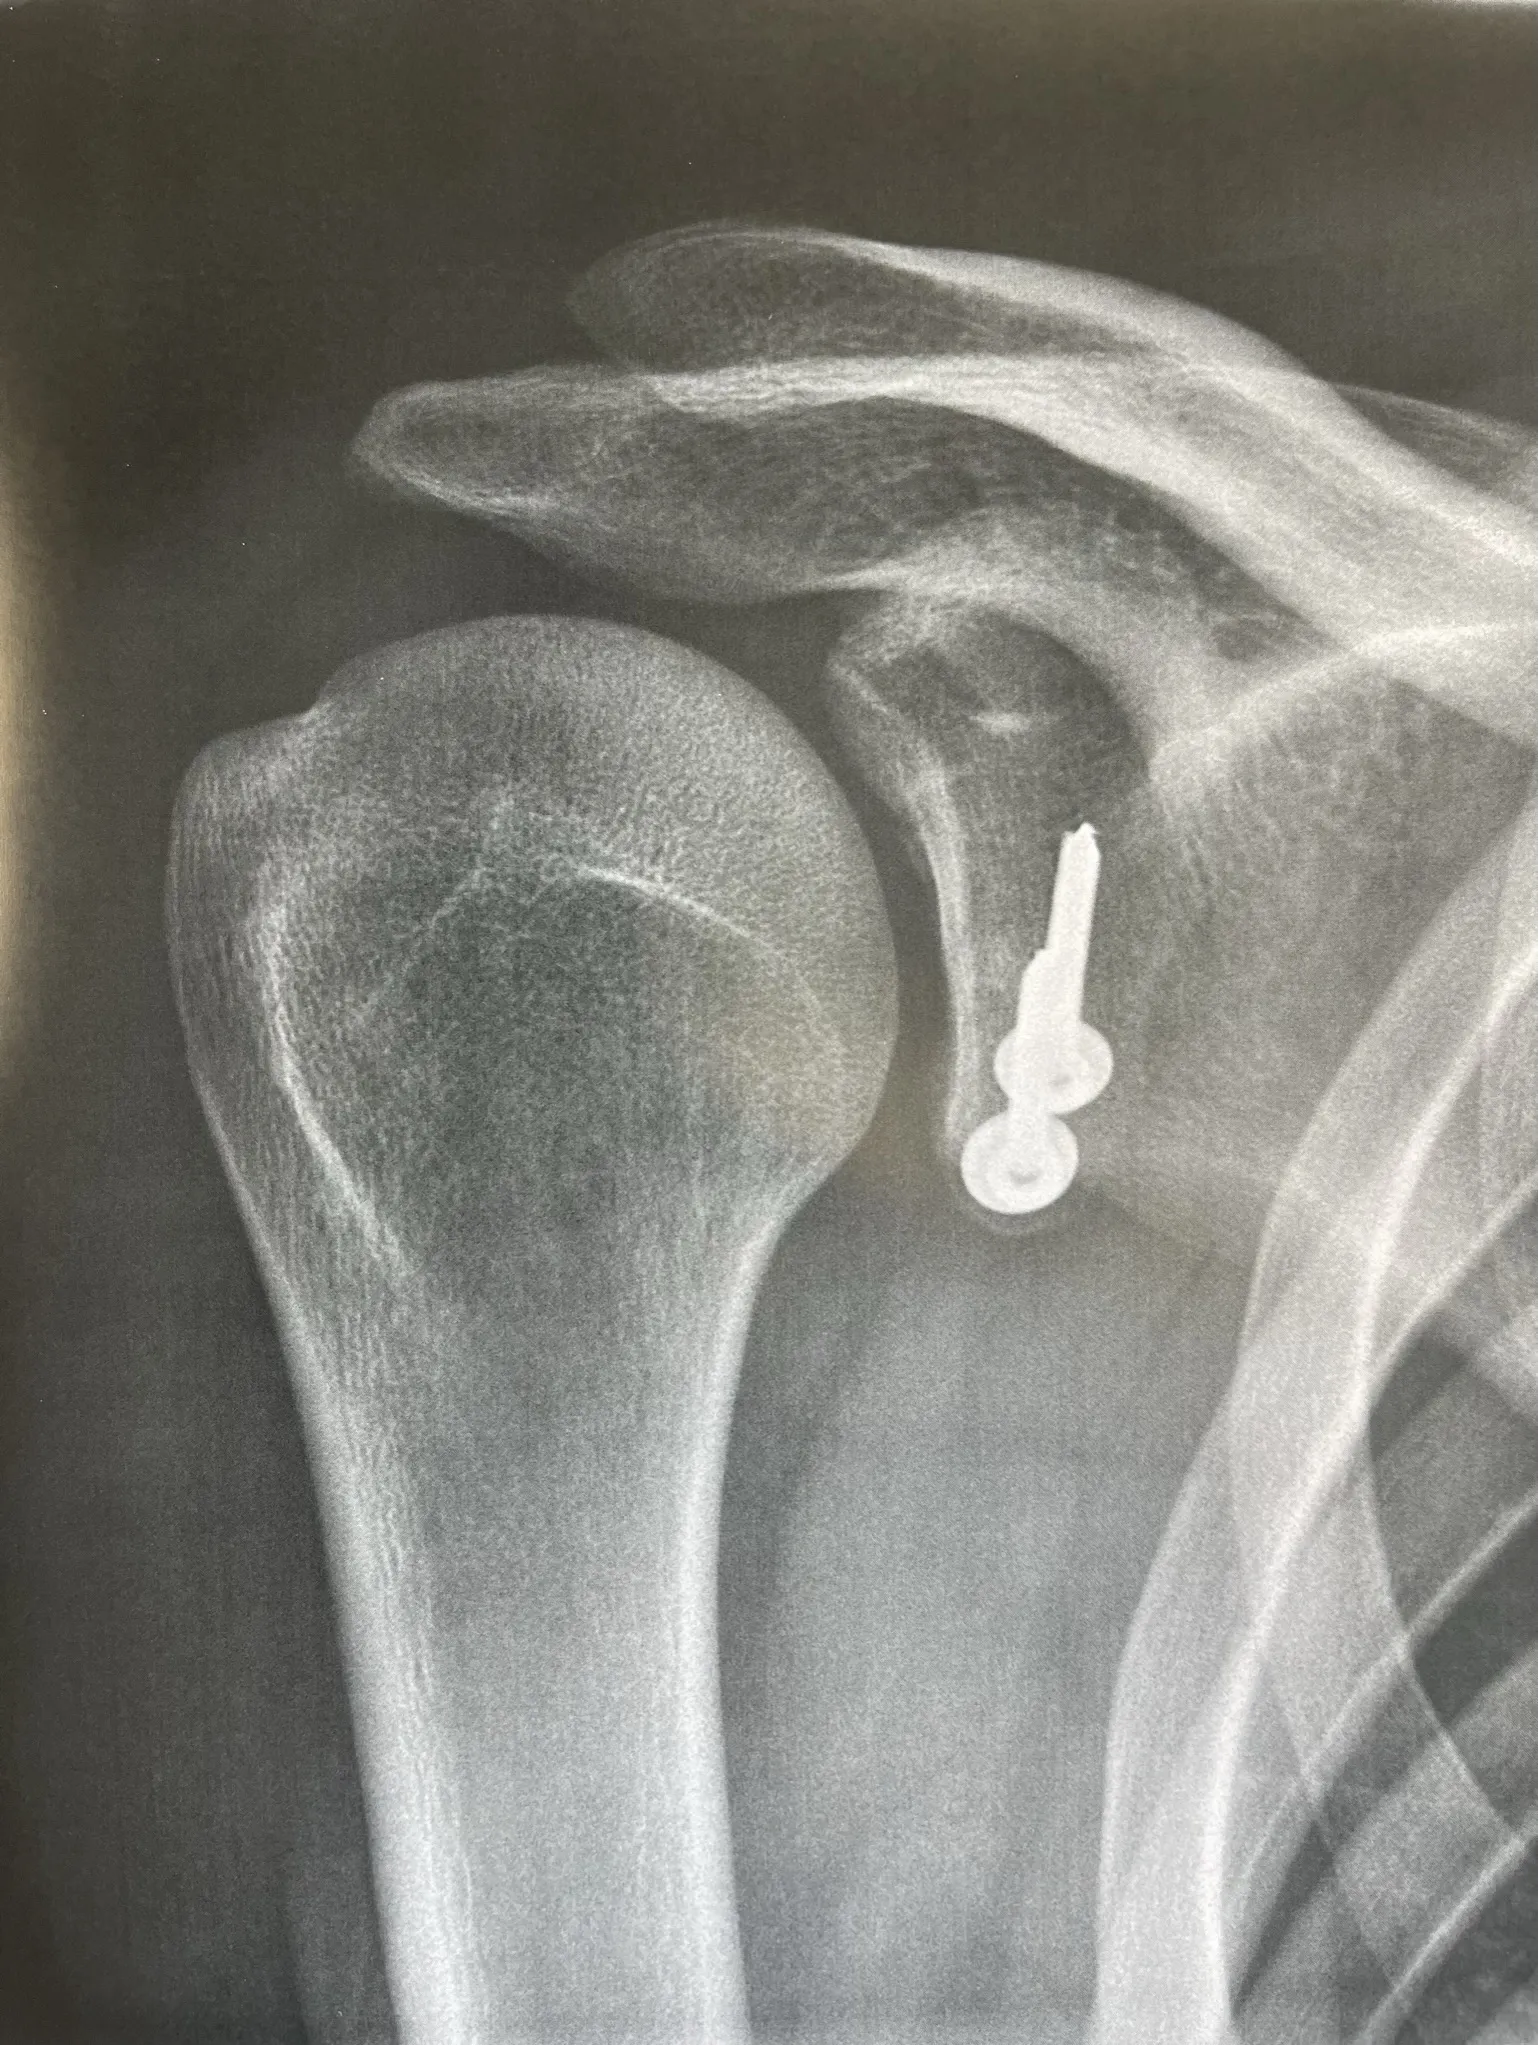

La butée coracoïdienne :

Cette intervention consiste à détacher un morceau d’os (la coracoïde) et à le refixer sur le bord antérieur de la glène afin d’obtenir un effet butée qui s'opposera à ce que la tête humérale ne reparte en avant de la glène. Cette butée est fixée par une ou deux vis ou par un système de boutons (endobutton). Elle est réalisée au travers d’une incision à la face antérieure de l’épaule de 5 cm environ.

La fixation de la butée peut se faire à l'aide de vis métalliques ou bien par des endobutton reliés par du fil très solide.

Depuis quelques années, cette technique peut également être réalisée sous arthroscopie par un chirurgien entrainé et formé. Votre chirurgien vous proposera cette technique si les lésions de votre épaule permettent de la réaliser.

Avant de remonter dans votre chambre vous passerez par la salle de réveil ou une radiographie de contrôle sera réalisée.

Vous reverrez le chirurgien au 45ème jour puis tous les 45 jours jusqu'à la fin de la rééducation avec des contrôles cliniques et radiographiques.